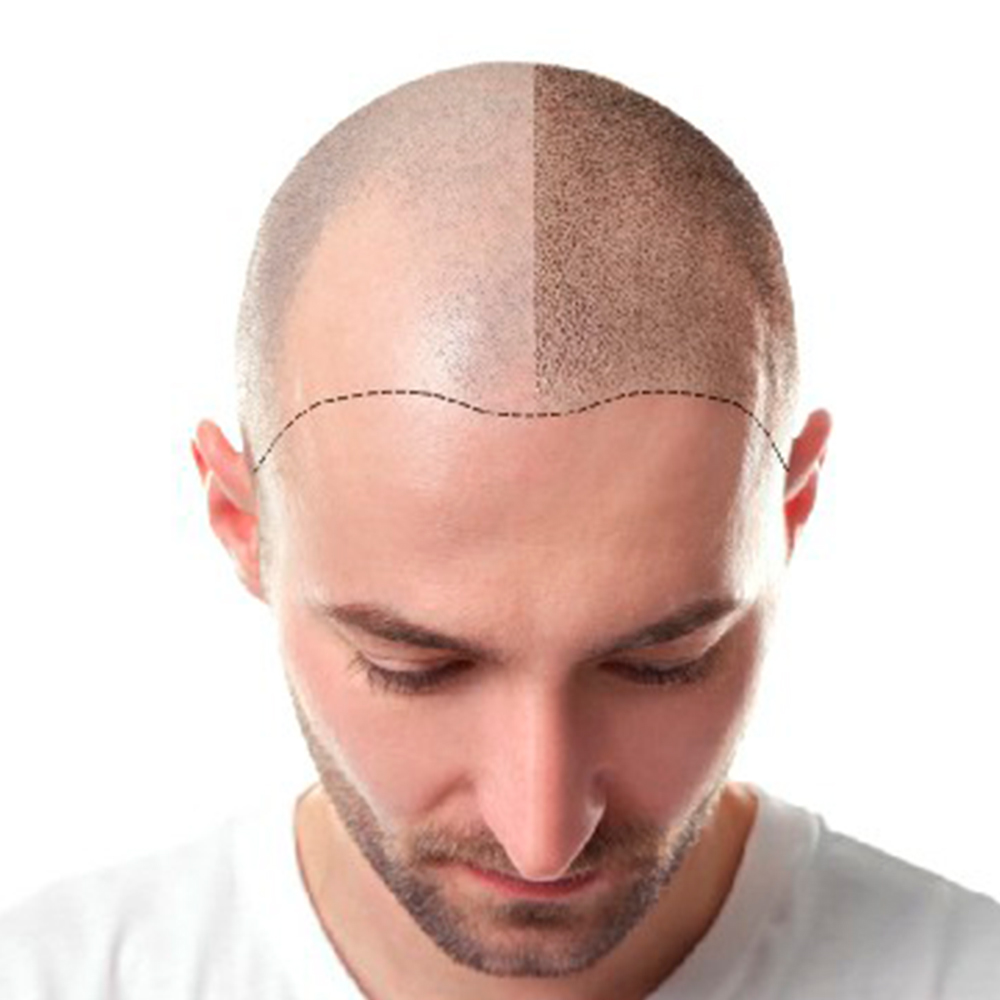

İşlemlerimiz

Önce-Sonra